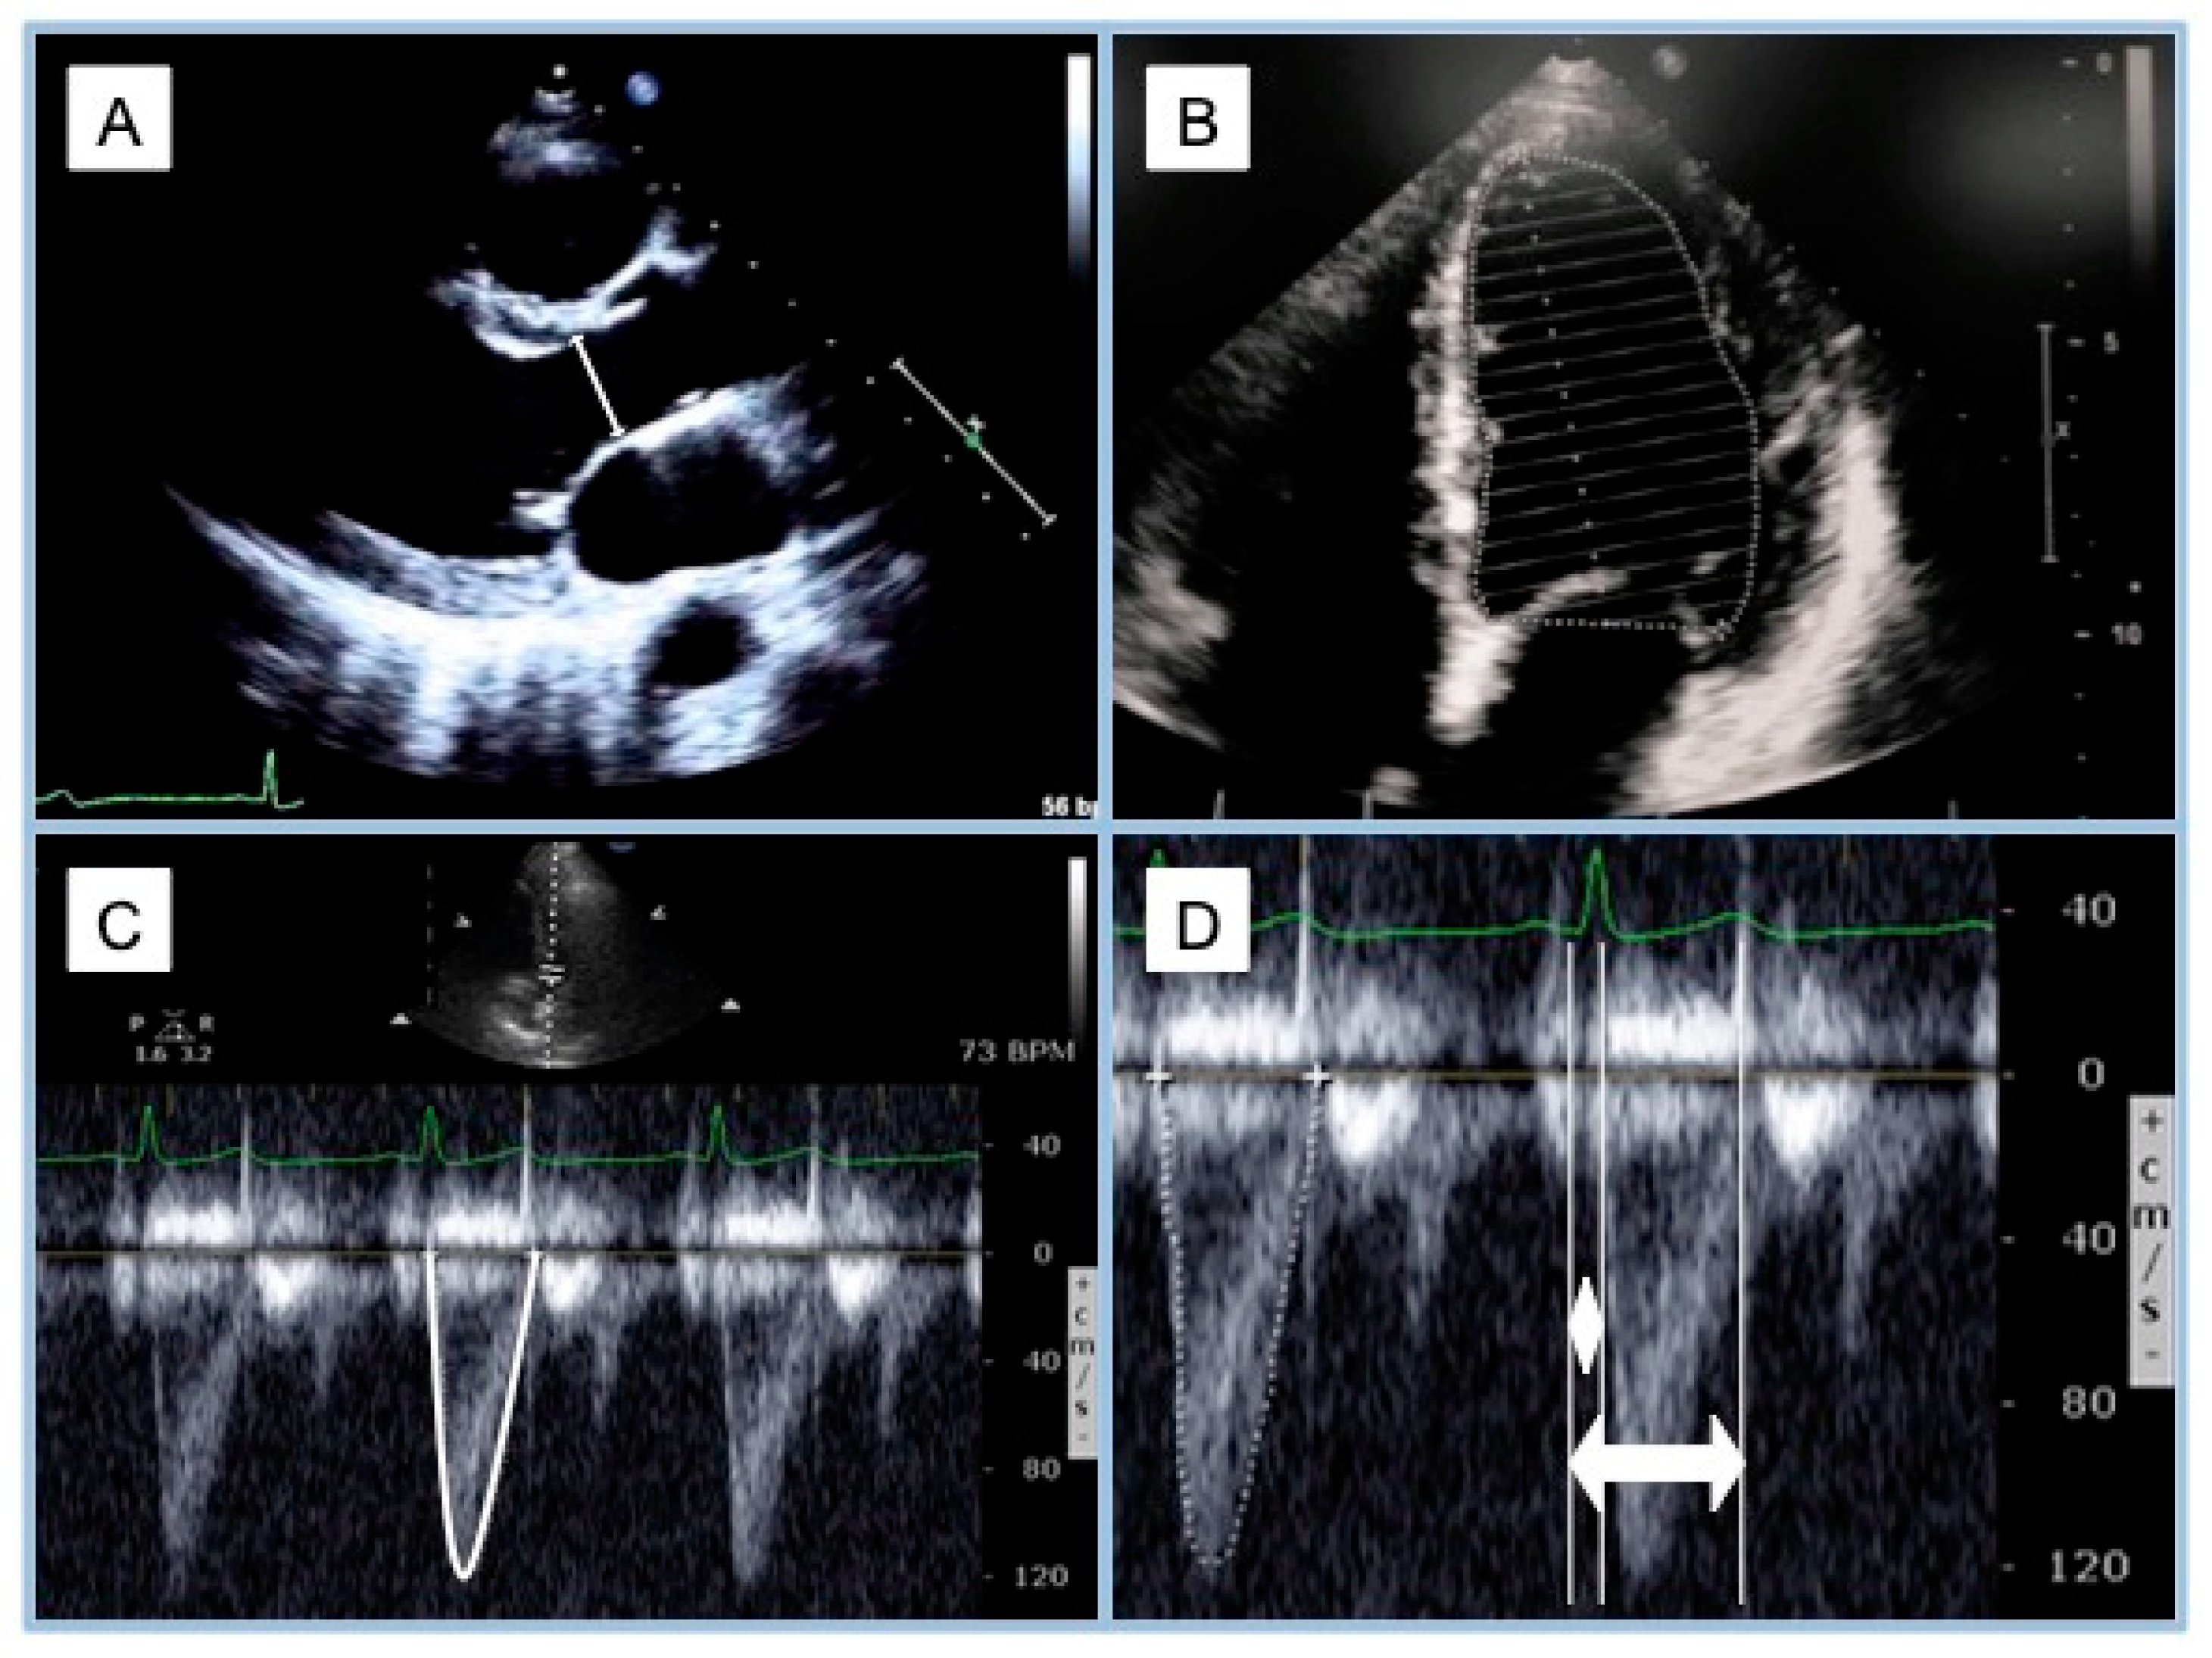

- Chen and colleagues [17] developed a method that is considered to be the non-invasive gold standard for Ees estimation. They compared invasive, conventional measures, which were estimated non-invasively in 50 individuals: 7 were healthy while 13 patients underwent coronary angiography without obstructive coronary artery disease (CAD) or ventricular dysfunction, 13 patients had CAD, 8 patients had hypertensive heart disease, 5 patients had dilated cardiomyopathy (DCM), 1 patient had hypertrophic cardiomyopathy (HCM), 1 patient had constrictive pericarditis, and 2 were heart transplant patients.